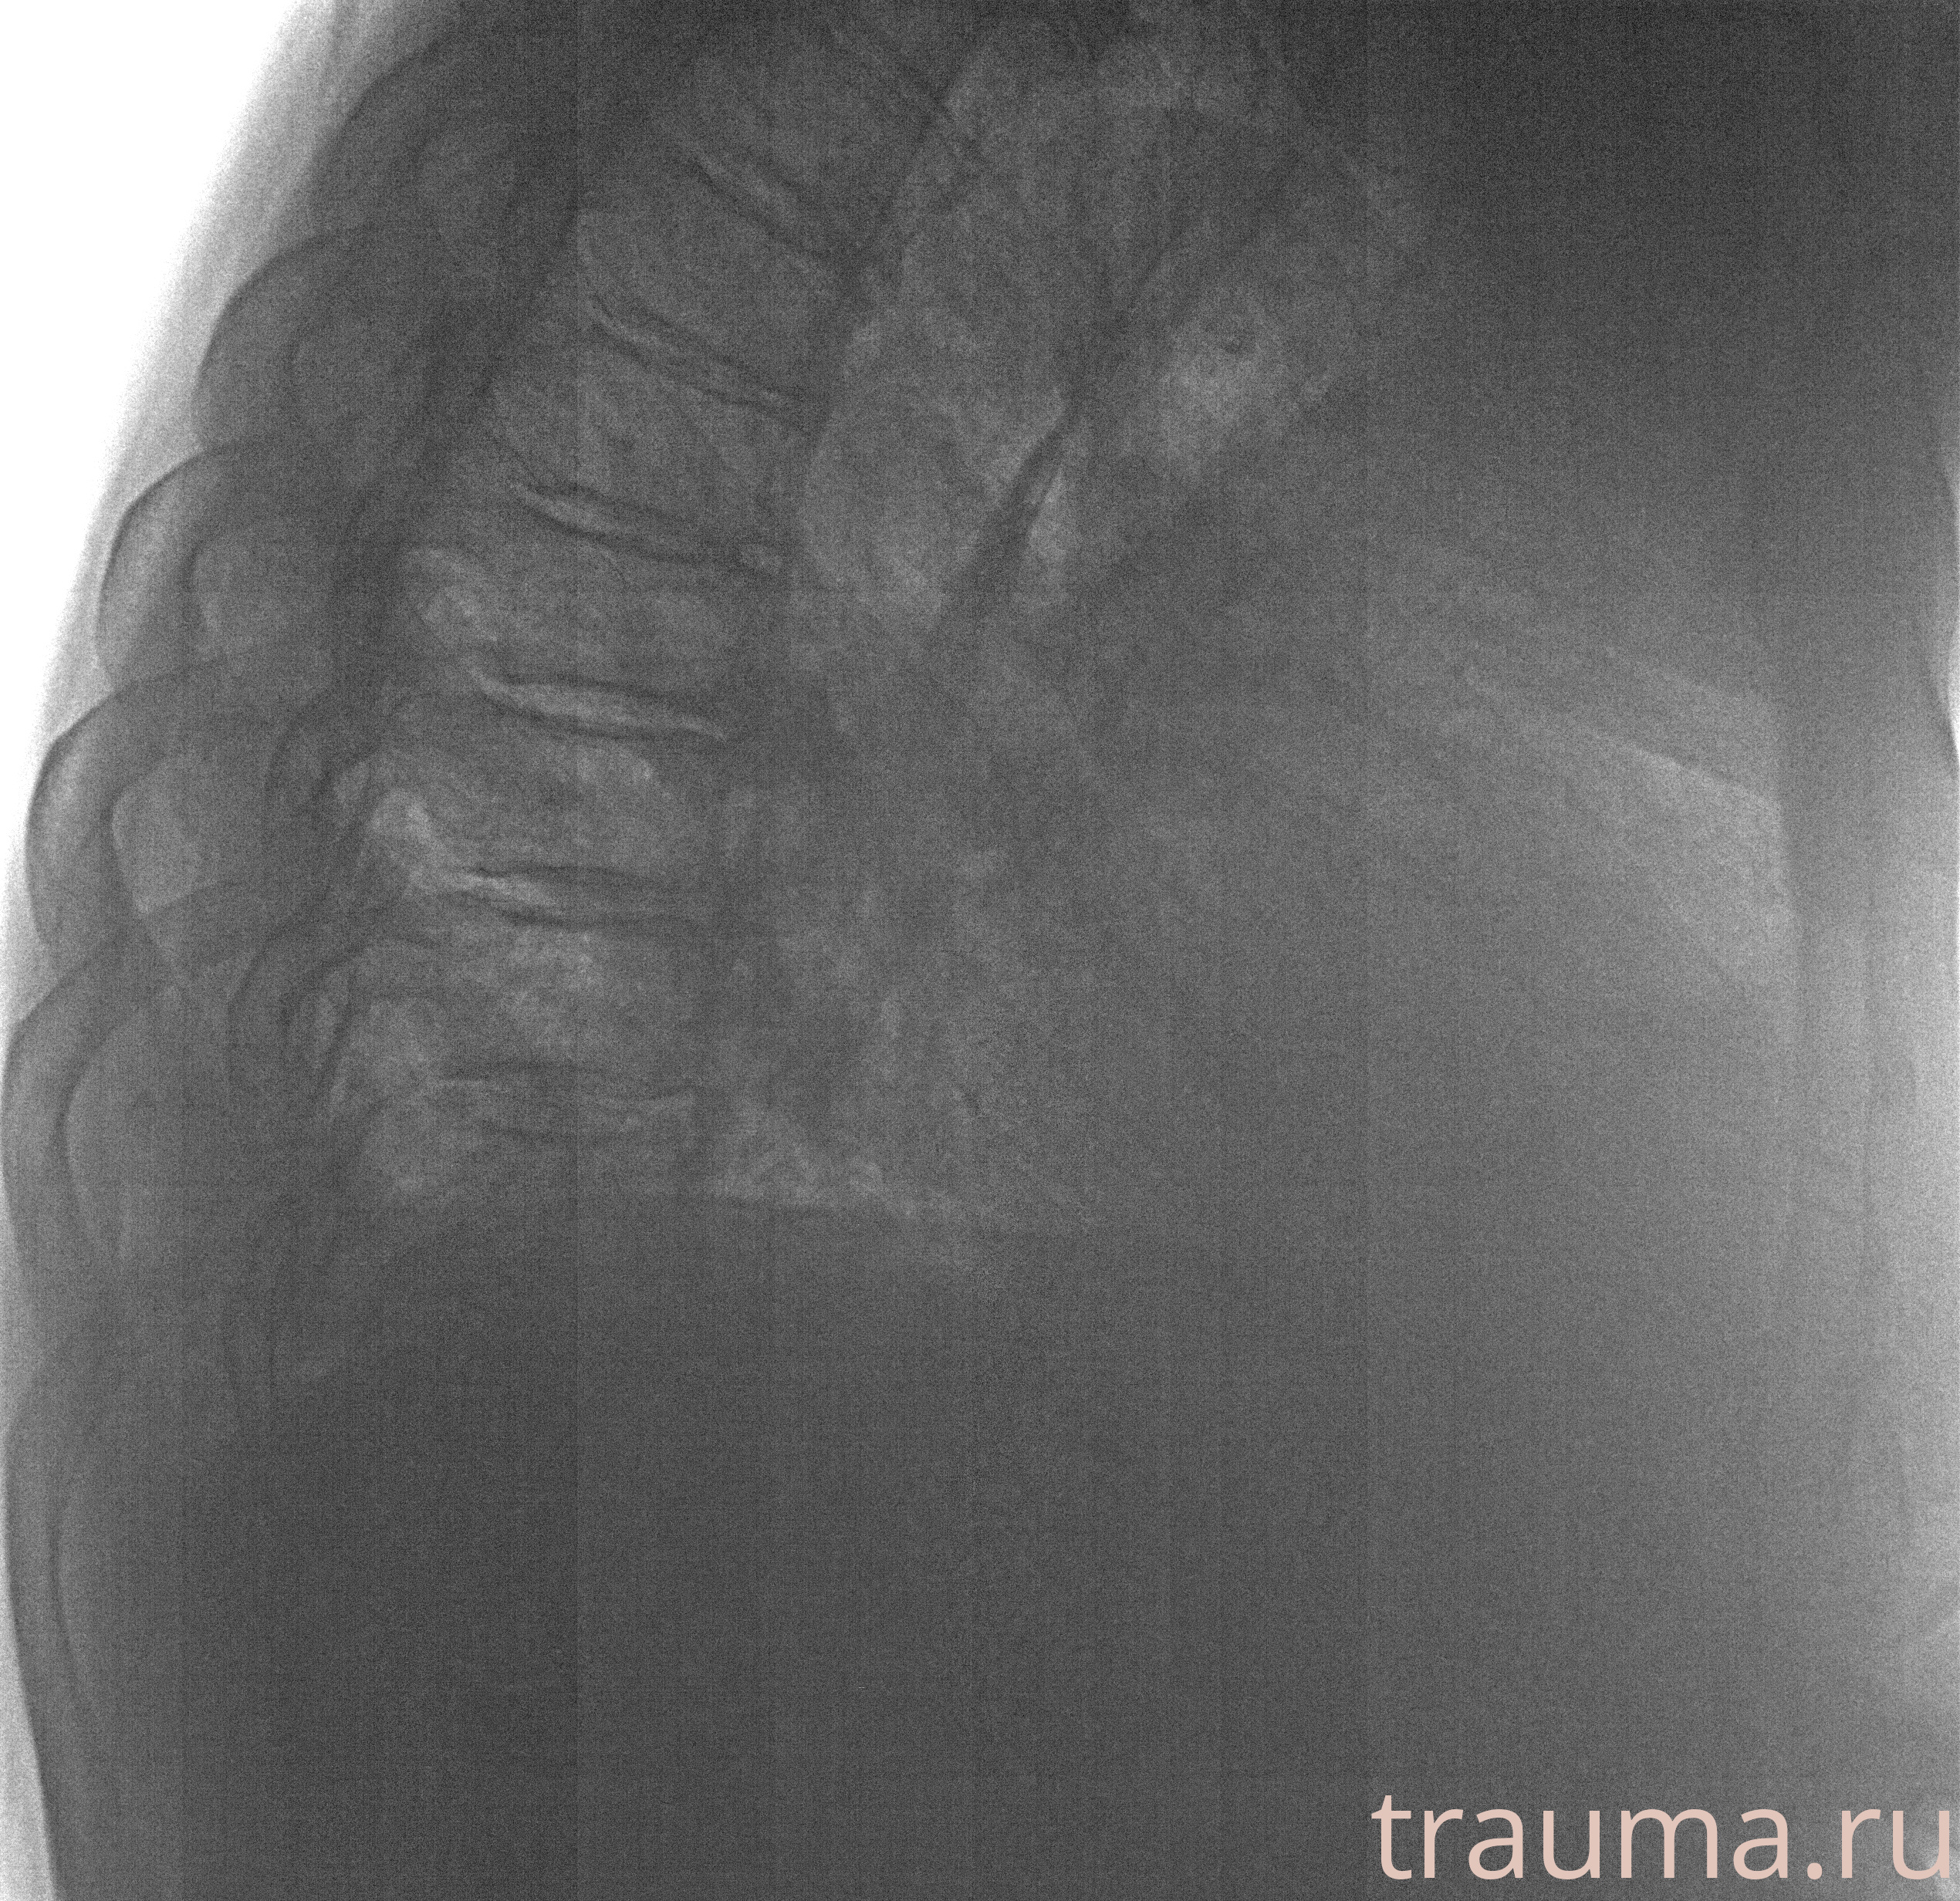

Рентгенограммы

Рентген на дому: по вашему адресу приезжает врач-рентгенолог, травматолог-ортопед с мобильным рентгеновским аппаратом, проводит диагностику травмы или заболевания, делает необходимые рентгенограммы, дает рекомендации по дальнейшему лечению. Получить качественные снимки в домашних условиях возможно благодаря уникальной методике, разработанной МосРентген Центром для института  Склифосовского